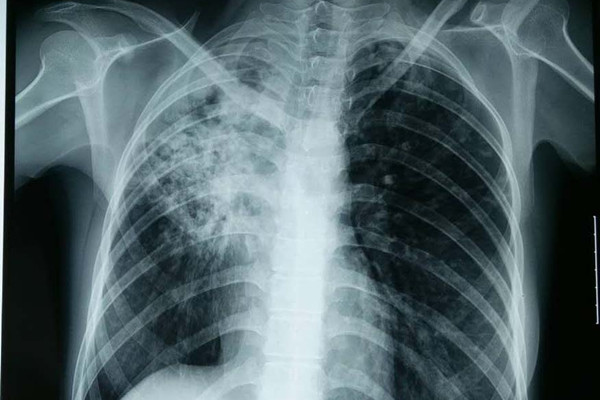

结核性胸膜炎一种慢性传染性疾病,为胸内淋巴结结核经淋巴途径、邻近肺及胸椎肋骨结核的直接侵犯、结核杆菌血行播散等所致。干咳和胸部疼痛以及呼吸困难,是结核性胸膜炎常见的症状表现,同时还可伴随发热、盗汗等结核病常见症状。

结核性胸膜炎根据症状特点可分为以下几类:干性胸膜炎,为胸膜的早期炎性反应,通常无明显的影像表现。渗出性胸膜炎,主要表现为胸腔积液。结核性脓胸,中毒症状明显,积脓较多时出现气急、呼吸困难等。结核性胸膜炎能治好吗,专家认为,根据不同疾病类型,采取科学、规范的治疗,遵循早期治疗、规律治疗、全程治疗、联合治疗的原则,结核性胸膜炎是可以很快治好的。